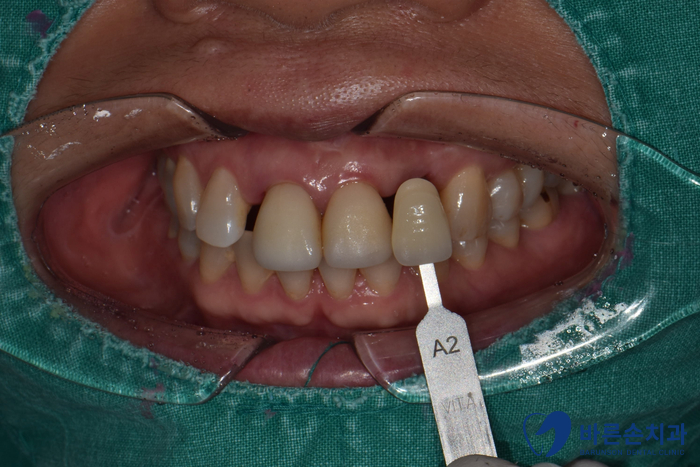

Before 25.08.26

치아색 확인 후 3D 구강스캐너로

보철을 만들어 옵니다!